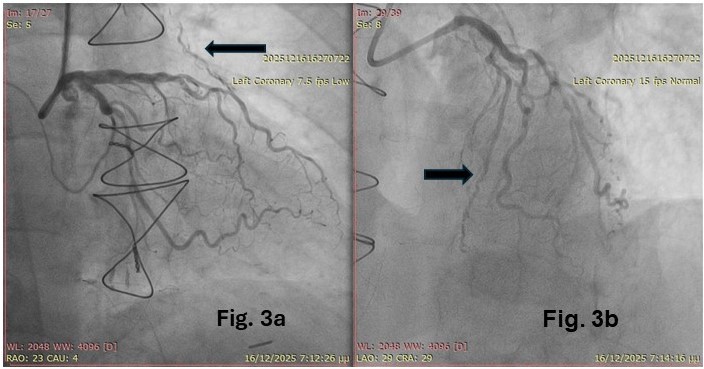

The second-stage PCI was performed via the right ulnar artery again. This revealed an open LAD (Figure 3B), despite its previous appearance of occlusion, while the LIMA graft now appeared diffusely narrowed (string sign) (Figure 3A). Dilation of the proximal LAD and stent placement concluded the second procedure (Video 3). The patient was discharged the next day without complications and remained asymptomatic at the 2-month follow-up.